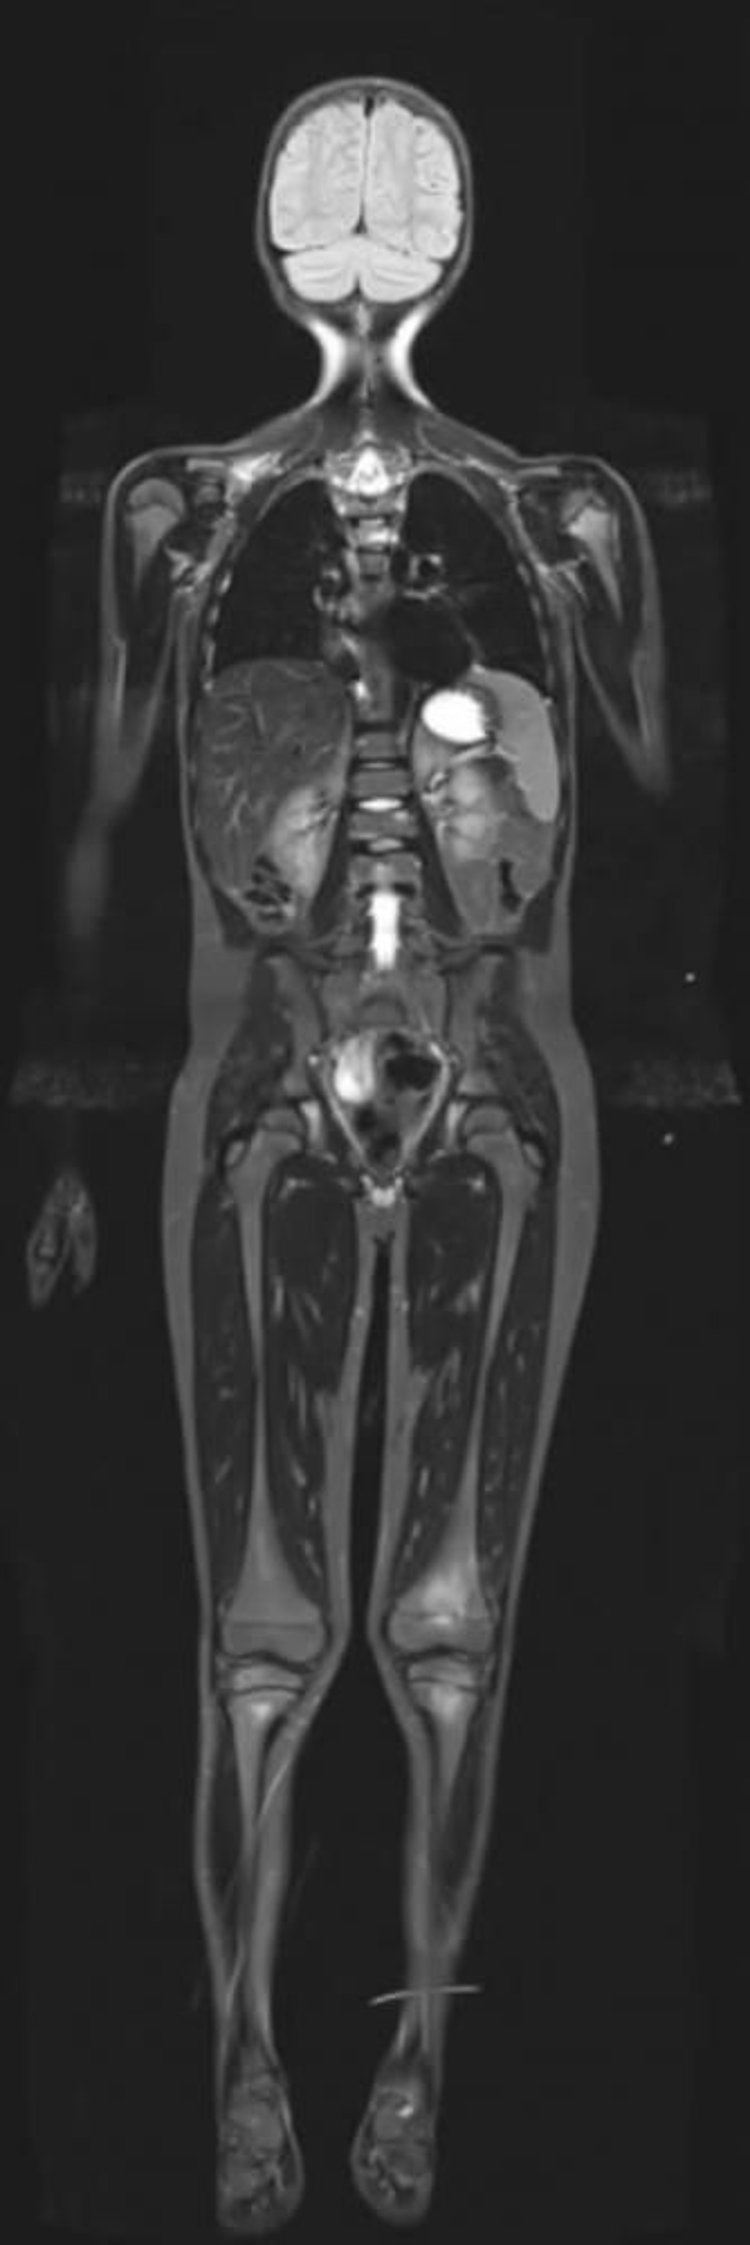

МРТ всего тела с использованием последовательности STIR (Short T1 Invertion-Recovery)

МРТ методом восстановления с инверсией с коротким T1 может подавлять сигналы от жировой ткани, что позволяет усилить сигналы с других тканей, имеющих высокое содержание воды.

Image courtesy of Hakan Ilaslan, MD.